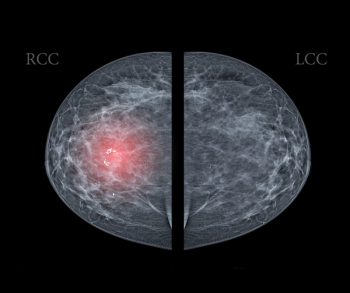

Researchers found the combination of magnetic resonance imaging (MRI) and contrast-enhanced mammography was nearly 22 percent more effective at detecting breast lesions than MRI-directed ultrasound.